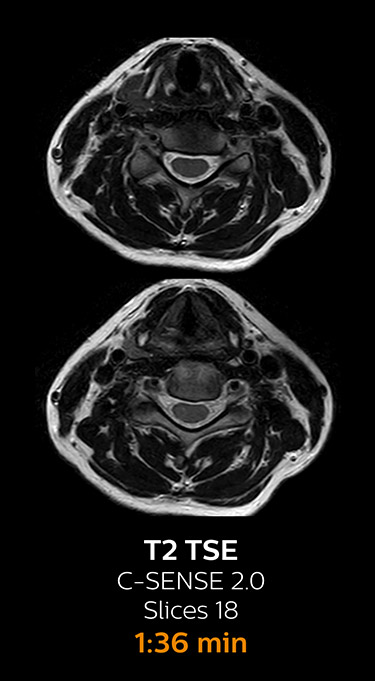

which corresponds to 34% reduction.

With Compressed SENSE, the scan time for the routine lumbar spine examination at KNC was reduced from 11:41 to 8:17 minutes,

MRI examination of the lumbar spine with Compressed SENSE

Ingenia 3.0T CX

Scan time 8:17 min. (was 11:41 min. without Compressed SENSE)